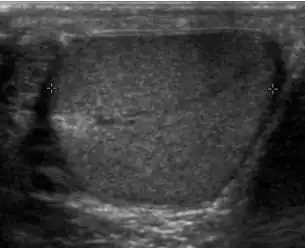

At ultrasound, the findings of acute epididymitis include an enlarged hypoechoic or hyperechoic (presumably secondary to hemorrhage) epididymis [Fig. 20a]. Other signs of inflammation such as increased vascularity, reactive hydrocele, pyocele and scrotal wall thickening may also be present. Testicular involvement is confirmed by the presence of testicular enlargement and an inhomogeneous echotexture. Hypervascularity on color Doppler images [Fig. 20b] is a well-established diagnostic criterion and may be the only imaging finding of epididymo-orchitis in some men.

Doppler ultrasound of epididymitis, seen as a substantial increase in blood flow in the left epididymis (top image), while it is normal in the right (bottom image). The thickness of the epididymis (between yellow crosses) is only slightly increased (7 mm). -

Doppler ultrasound of the scrotum of the same case, in the axial plane, showing orchitis (as part of epididymo-orchitis) as hypoechogenic and slightly heterogenic left testicular tissue (right in image), with an increased blood flow. There is also swelling of peritesticular tissue.